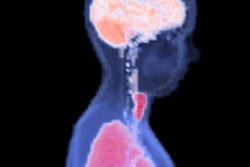

Between 2014 and 2020, she was a part-time PhD student at Lund University, while still working at the 7-tesla scanner. She defended her doctoral thesis, "Safety and Health Effects in High and Ultra-High Field MR," in September 2020.